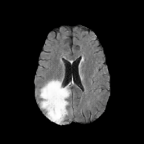

Brats MRI T1 Scans, FLAIR, Tumors. Lastly, we used a dataset of brain MRI scans [28] with two modalities: T1 (naive) and FLAIR (T2 Fluid Attenuated Inversion Recovery) [15]. We adapt the protocol that Cohen et al. [9] used for the Brats2013 datasets [27] to the more recent Brats2018 [3] dataset by varying the percentage of scans with tumors in the target domain. We selected transverse slices from the to range in the caudocranial direction [1] for both T1 and FLAIR scans. Each scan was classified as tumorous if more than of its pixels were labeled as such, and as healthy if it contained no tumor pixels. The training set contains images from each modality, with all source images (T1) being healthy and the target domain (FLAIR) comprising tumorous scans. The test set contains paired scans of healthy brains.

We label each scan as tumorous if more than of its pixels are labelled as such, and as healthy if it contains no tumor pixels. We only use high-grade gliomas (HGG) instead of low-grade gliomas (LGG) as the are more easily observable [24]. In total, we obtain 5035 pathological pairs and 1135 healthy pairs. The train set is composed of a source domain of T1 images of healthy brains, while the target domain set is composed of FLAIR scans of which (60%) are tumorous and healthy. The test set is composed of aligned scans of healthy brains in both modalities.